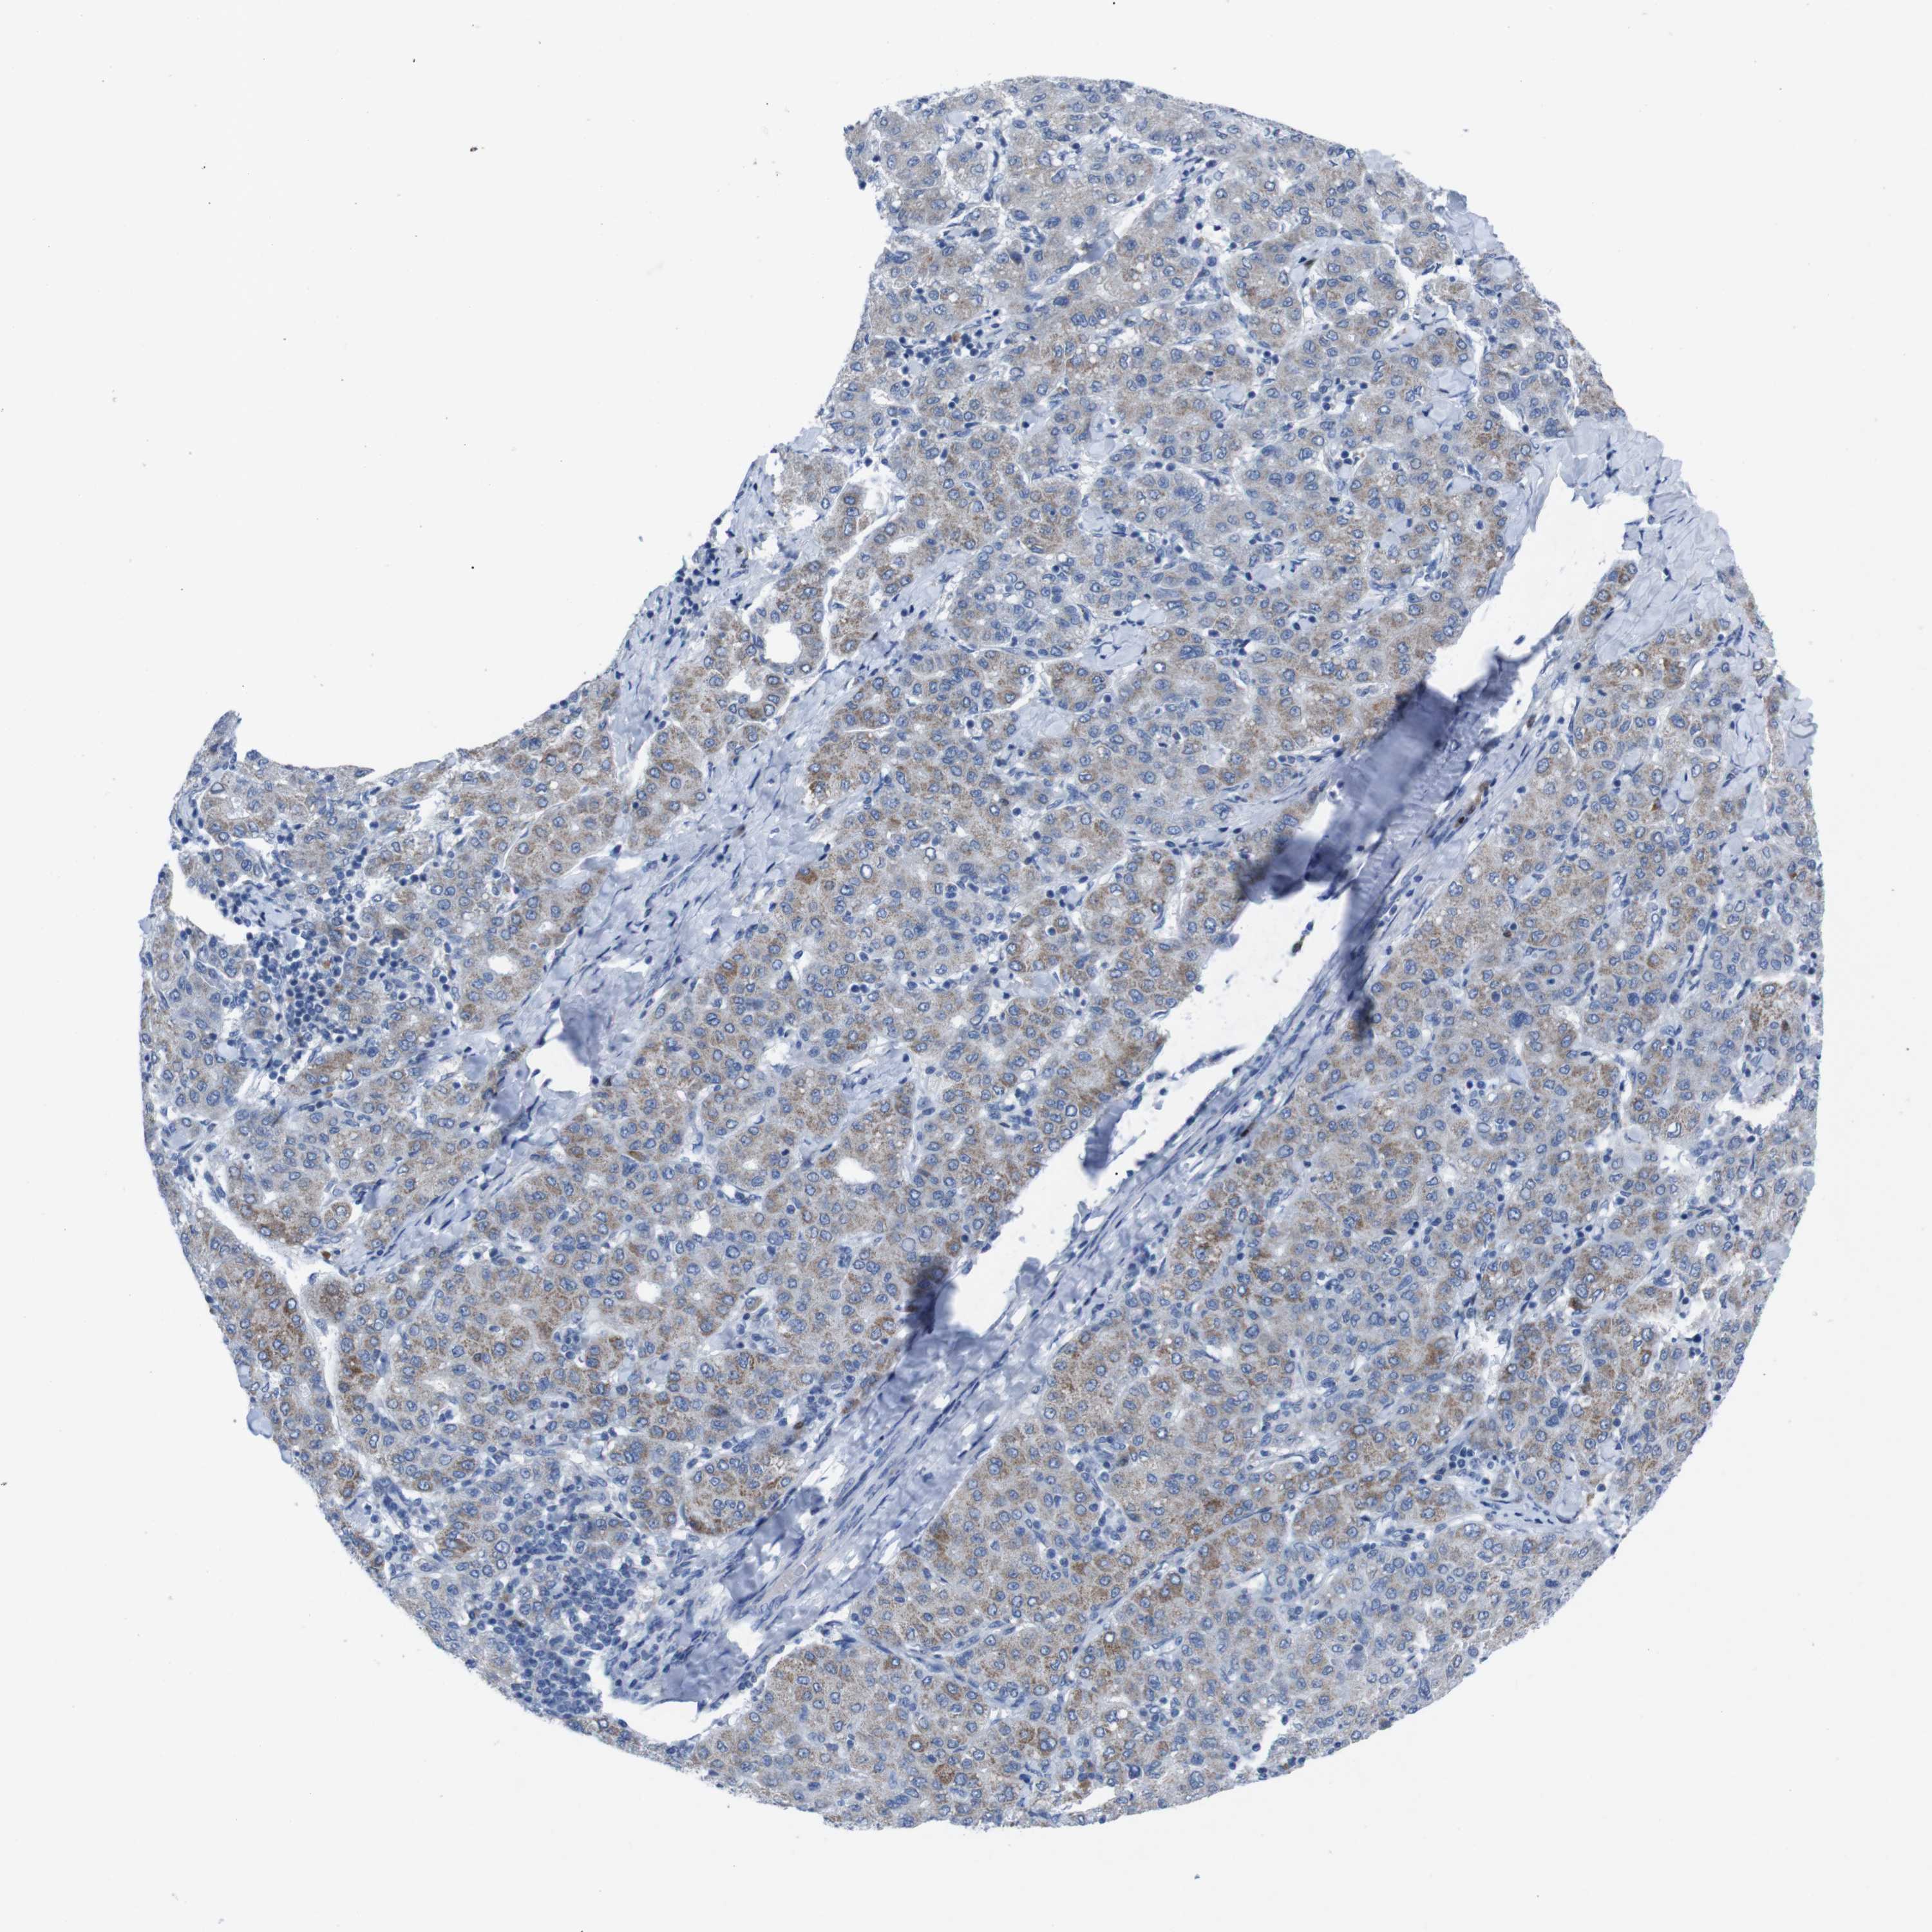

LIVER CANCER - Protein expressioni

A mouse-over function shows sample information and annotation data. Click on an image to view it in a full screen mode. Samples can be filtered based on level of antibody staining by selecting one or several of the following categories: high, medium, low and not detected. The assay and annotation is described here.

Note that samples used for immunohistochemistry by the Human Protein Atlas do not correspond to samples in the TCGA dataset.

Antibody stainingi

Antibody staining in the annotated cell types in the current human tissue is reported as not detected, low, medium, or high, based on conventional immunohistochemistry profiling in selected tissues. This score is based on the combination of the staining intensity and fraction of stained cells.

Each image is clickable and will lead to virtual microscopy that enables deeper exploration of all samples and also displays staining intensity scores, fraction scores and subcellular localization as well as patient and tissue information for each sample.

Antibody HPA002038

Antibody HPA002698

Antibody CAB013508

Staining

High

Medium

Low

Not detected

Intensity

Strong

Moderate

Weak

Negative

Quantity

>75%

75%-25%

<25%

None

Location

Nuclear

Cytoplasmic/membranous

Cytoplasmic/membranous,nuclear

Cholangiocarcinoma

Carcinoma, Hepatocellular, NOS